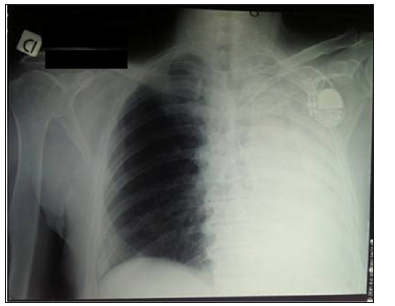

A 65-old Italian man was admitted at 4 pm to the emergency department presenting worsening dyspnoea developed two days before during the normal daily activities. Significant alcoholism and tobacco smoking story was noted. The past medical history consisted of anxiety and depression, epidermoid tongue cancer treated by pull through operation, extended right cervical lymphadenectomy and temporary tracheotomy in 2011 (pT1N0G3), chronic cerebral vasculopathy and pace-maker implantation for trifascicular block. General examination revealed a mild cooperative and pale male. The oral cavity presented the surgical sign of previous partial tongue resection and neck examination showed the signs of previous tracheotomy (Figure 1). Respiratory examination revealed patient affected by dyspnoea and reduction of breath sounds in the left hemithorax. Cardiovascular auscultation revealed arrhythmic heart sounds. Abdominal examination was unremarkable. The patient presented altered vital signs: artery pressure of 140/80 mmHg; arrhythmic pulse of 112 bpm; arterial oxygen saturation of of 74% a/a. He was not febrile. Abnormal laboratory investigations included: white blood cells 17.1 x103/uL (4.00-10.00); D-Dimer 352 ng/ml (< 278); Glycemia 197 mg/dl (70-110); NT-pro BNP 2741 ng/L (<450); cardiac T troponin 21.12 ng/L (0-14); reactive C protein (RCP) 94.1 mg/L (0-5). Electrocardiogram showed atrial fibrillation. Chest X-ray (CXR) was performed in supine position and demonstrated complete opacification of the left hemithorax with shift of cardiac structures to the left side, hyperexpansion of the right lung, no estimable cardiac imaging, no pleural effusion on the right, pace-maker device on the left side (Figure 2). The arterial blood gas analysis showed: pH 7.52; PaCO2 24.1 mmHg; PaO2 34.6 mmHg; arterial oxygen saturation of 73.9%; lactates 3.1 mmol/L; HCO3- 20.1 mmol/L; BEecf -3.0 mmol/L; PaO2/FiO2 165.7 mmHg. Antibiotic prophylaxis (Ceftriaxone 1 g and Metronidazole 1500 mg) and oxygen therapy (FiO2 1) were given.